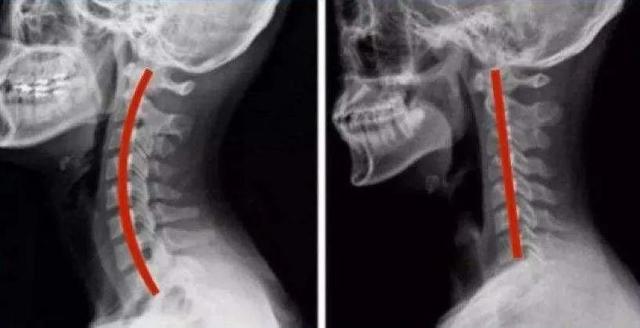

正常的脊柱不是一条直线,而是一条完美的生理曲线,颈椎和腰椎前凸,胸椎后凸。

从侧面看,正常第2~7颈椎形成的向前凸起的弧度,称为“颈椎生理前凸”。

当长期坐姿不正确、劳累、枕头过高、颈椎一直处于反曲状态的高度疲劳之下,缺少活动或损伤,就会引起颈部疼痛、痉挛,导致颈椎生理曲度变直,是颈肩痛最常见的原因之一。